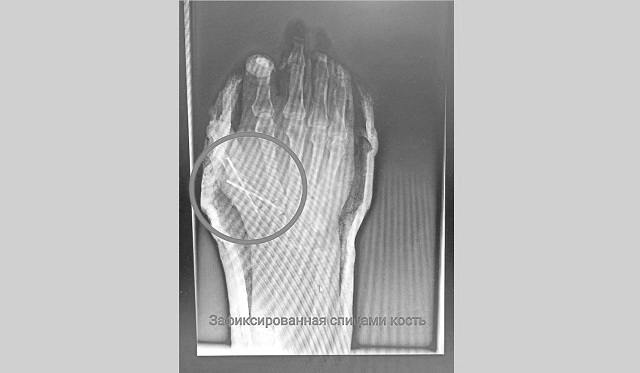

Медики пояснили, что мужчина получил резаную рану правой кисти с повреждением сухожилия большого пальца и открытый перелом основания пястной кости со смещением.

В экстренном порядке мужчину прооперировали. Травма оказалась сложной, мужчина мог лишиться большого пальца, который почти полностью был отрезан от руки. Врач восстановил сначала пястную кость, зафиксировав ее спицами, потом аккуратно восстановил сухожилия. Операция продлилась 2,5 часа.